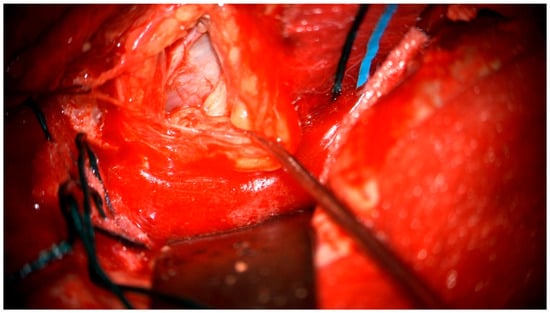

After the lumbar drainage was inserted, the patient was positioned in a supine position, with the head fixated in a Mayfield clamp and turned to the right. Neuronavigation based on previous MRI was used to mark the incision. A left-sided pterional craniotomy was performed to access the eye socket; a resection of part of the superior orbital wall was performed. With a surgical microscope, the intraorbital dura mater was opened. The pathological tissues appeared in a light gray color, tissues were loose, and the tumor was fragmented and aspirated with the help of a CUSA (cavitronic ultrasonic surgical aspirator) (Figure 5). After closure of the dura mater, the orbital wall was reconstrued with an individually mended standard titan orbital wall implant, which was fixated with three mini screws. Under the microscope, pathological tissues in the medial brain fossa were visualized and resected subtotally.

The tumorous tissue (1.5 cm × 0.5 cm × 0.3 cm) was extracted during the surgery and delivered to the pathology laboratory (Figure 6).

Figure 6. The tumorous tissue extracted during the surgery.